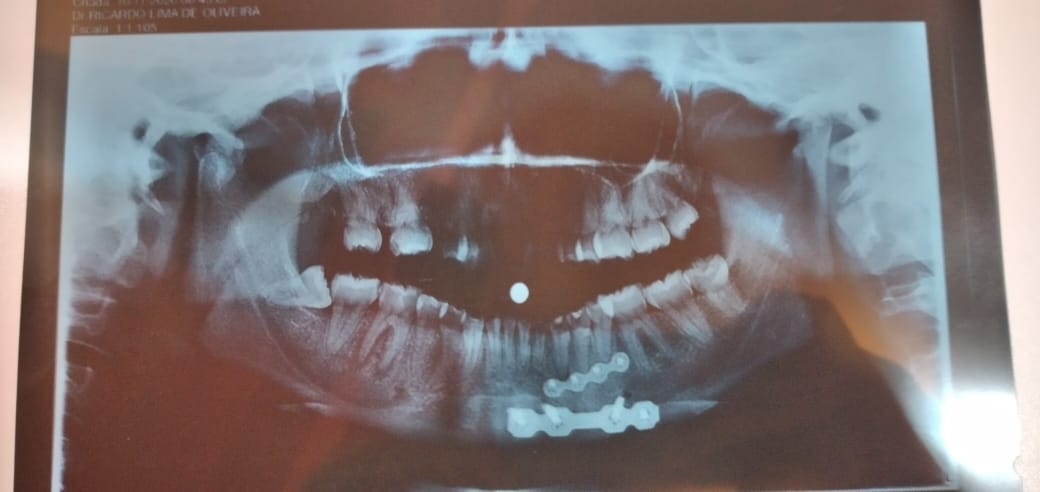

Tendo sido socorrido para o Hospital Regional de Patos, ela passou 10 dias internadas. Ela quebrou a mandíbula. Foi feito uma cirurgia e após o décimo segundo dia ela retornou para casa, onde teve complicações. Infecções fizeram da vida de Ludmila um verdadeiro sofrimento.

A placa ficou infeccionada e a jovem agora tem que fazer uma nova cirurgia, porém por conta dos leitos lotados com casos de covid-19, precisará desembolsar o valor de R$4mil para o tratamento um ano e cinco meses após o acidente em uma clínica particular. Manchas vermelhas surgem por todo o corpo da jovem.

A mãe conta que a jovem perdeu vários dentes e que foi necessário usar uma prótese. As dificuldades na casa não são apenas com a jovem. A mãe dela perdeu completamente a visão e Ludmila se tornou uma aliada nos serviços da casa.